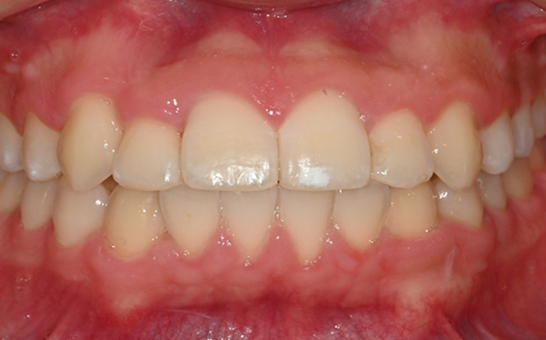

인비절라인 퍼스트(Invisalign First)는 어린이와

성장기 청소년을 위한 투명 교정 장치로, 치아와 턱뼈가

성장하는 과정에 맞춰 설계된 교정 시스템입니다.

해당하는 증상이 있다면 전문의와 상담 후 조기 교정 시

성장기 어린이에게 교합이 틀어지는것을 미리 예방 할 수 있습니다.

※ 바른선택치과의원은 의료법을 준수하며 위 케이스는 실제 내원 환자분의 동의하에 공개된 사진과 동일한 환자분께 같은 조건에서 촬영한 사진을 활용했습니다.

개인에 따라 진료 및 치료 방법이 다르게 적용할 수 있으며, 효과와 부작용이 개인마다 다르게 나타날 수 있는 점을 안내해 드리며, 진료 전 전문의료진과 충분한 상담을 권해드립니다.